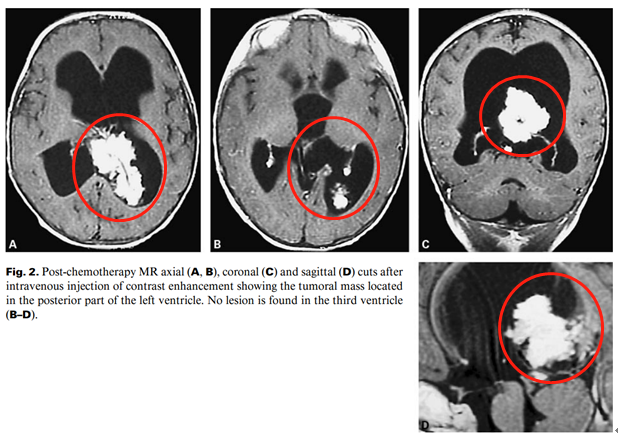

颅脑MR显示侧脑室及第三脑室内的脉络膜丛乳头状瘤

化疗后磁共振轴位(A, B)、冠状位(C)、矢状位(D)在静脉注射增强后显示位于左脑室后部的肿瘤肿块。

在接受化疗3个月后,检查显示肿瘤体积略有缩小。然而,这种轻微的大小变化与肿瘤位置的显著变化有关。此时肿瘤实际位于侧脑室,第三脑室并未受累,于是,Di Rocco教授及时调整了手术入路,采用左后顶骨入路,允许控制后方放置的供血动脉,为患儿成功全切肿瘤。